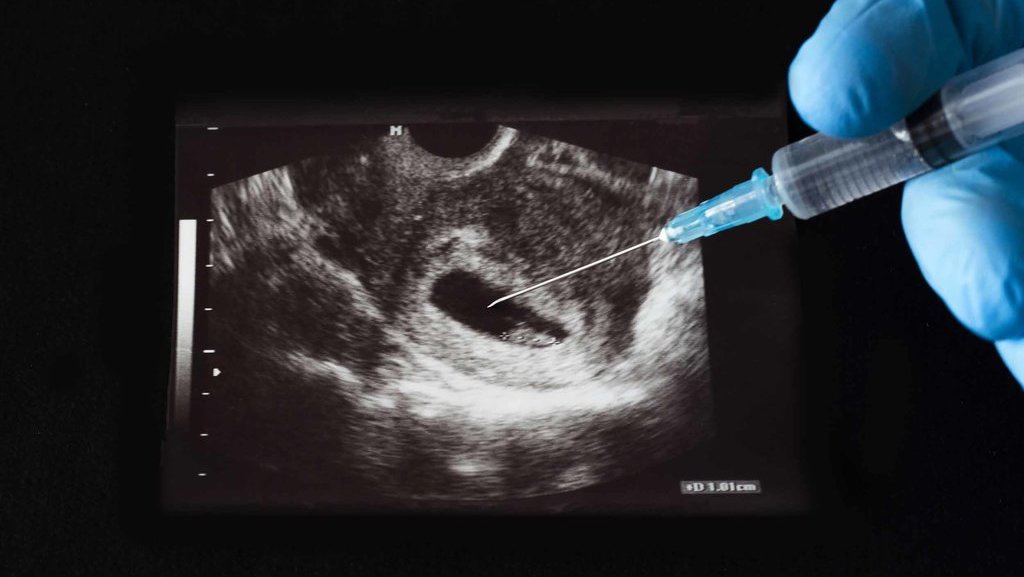

tirto.id - Kementerian Kesehatan (Kemenkes) membuka peluang fasilitas kesehatan (faskes) swasta boleh melakukan aborsi sebagai tindak lanjut Peraturan Pemerintah Nomor 28 Tahun 2024 tentang Kesehatan yang mengatur soal aborsi. Akan tetapi, Kementerian Kesehatan lebih mendorong rumah sakit pemerintah dan rumah sakit kepolisian yang boleh memberikan layanan aborsi.

Sebelumnya, pemerintah menerbitkan PP Nomor 28 Tahun 2024 pada 26 Juli 2024. Salah satu poin yang menjadi sorotan adalah pengaturan tentang aborsi yang dibolehkan bagi perempuan hamil dengan indikasi kedaruratan medis serta korban tindak pidana pemerkosaan atau tindak pidana kekerasan seksual lainnya yang menyebabkan kehamilan. Ketentuan tersebut tertera pada Pasal 116 PP Kesehatan.

Mengenai penunjukan fasilitas kesehatan, Pasal 119 ayat 1 PP Kesehatan menyatakan bahwa pelayanan aborsi yang diperbolehkan hanya dapat dilakukan pada Fasilitas Pelayanan Kesehatan tingkat lanjut yang memenuhi Sumber Daya Kesehatan sesuai standar yang ditetapkan oleh Menteri.